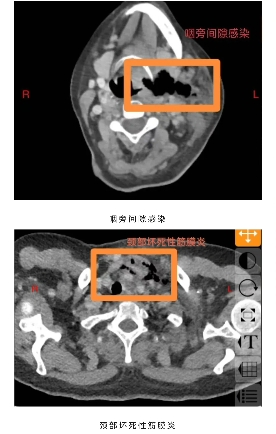

阳光讯(记者郑亚雷 通讯员 陈萌)60岁的庄女士未曾想到,一场看似寻常的牙痛,竟会迅速发展为危及生命的重症。庄女士糖尿病多年未经规范治疗,口腔卫生欠佳,口内牙齿时不时疼痛、松动、脱落,患者总认为牙疼是小毛病,吃点甲硝唑就好了,从未重视。5 天前,左下后牙疼痛后患者依旧未经重视,很快就出现咽部、颈部疼痛伴吞咽困难,在当地医院接受抗感染治疗,病情却未见好转,还出现难以忍受的胸部疼痛,叠加吞咽、呼吸困难等症状,被救护车紧急送往西安市红会医院耳鼻咽喉头颈整形修复科。经诊断,庄女士为 “颞下、咽旁、翼下颌、颌下间隙感染,颈部坏死性筋膜炎、下行性坏死性纵膈炎”,病情及其危重,需要头颈外科、胸外科、内分泌科等多学科联合救治,此类疾病非常凶险,死亡率较高,为患者办理住院后转入急诊重症监护室(EICU),一场与死神的赛跑就此拉开序幕。

耳鼻咽喉头颈整形修复科龚龙岗主任、马戈副主任团队第一时间全面评估病情,发现庄女士不仅存在口腔颌面多间隙感染,还并发左侧颈部坏死性筋膜炎、下行性坏死性纵膈炎、右侧包裹性脓胸,叠加2型糖尿病(血糖控制不佳)、高血压病1级(极高危)、电解质紊乱等基础疾病与并发症,病情复杂凶险。面对这一局面,科室迅速启动多学科联合救治机制,一场跨科室的协同作战即刻展开 —— 胸部外科、EICU、内分泌代谢科、神经内科、营养膳食科等科室专家迅速集结,从各自专业维度切入,共同为庄女士制定个性化救治方案。